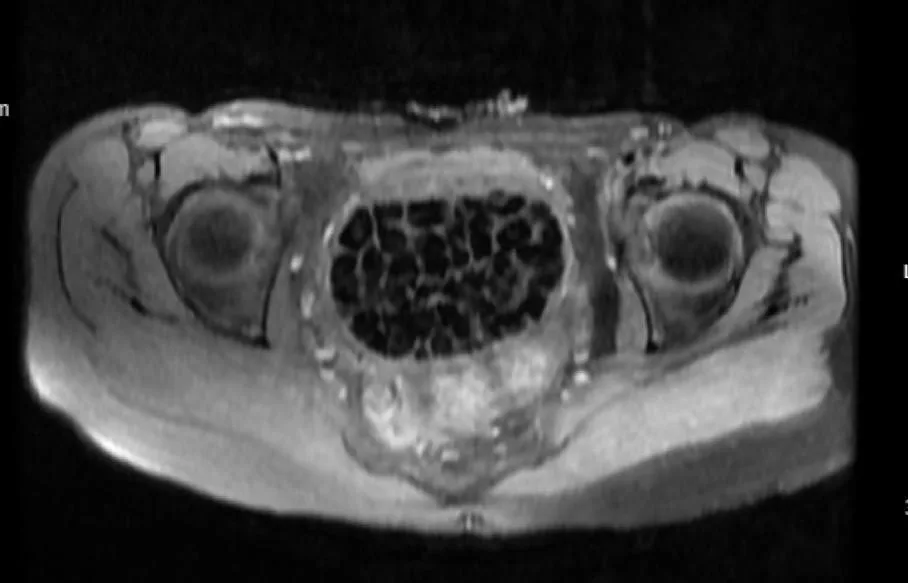

Turkish Doctors Remove 287 Stones From Young Woman

In Türkiye, 21-year-old Fatma Nur Öztürk underwent surgery after severe abdominal pain revealed a rare condition. Doctors discovered and removed 287 stones, the largest measuring 2.5 centimeters, from her bladder and vaginal area.